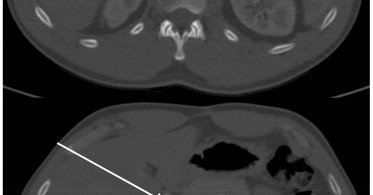

π©»β οΈ Rare trauma complication. This case highlights endovascular repair of a hepatic artery pseudoaneurysm with celiac dissection & intramural hematoma after blunt abdominal trauma, showing the power of minimally invasive management. π https://t.co/F9sOXcp1OU

#VascularTrauma

jvscit.org

Hepatic artery pseudoaneurysm is a concerning yet rare complication of blunt abdominal trauma, with treatment recommended upon diagnosis.1 Endovascular repair of hepatic artery aneurysms has gained...